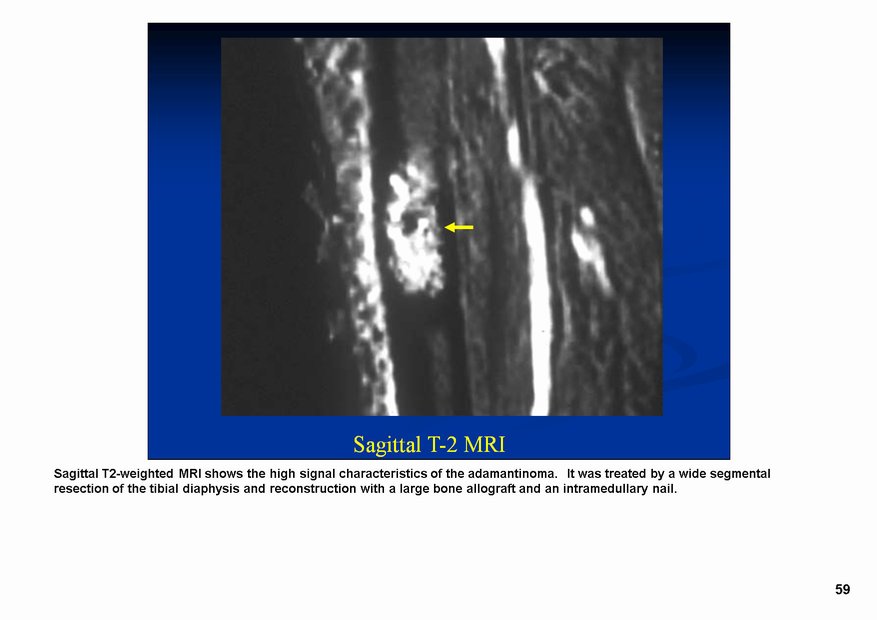

Классический радиологический облик